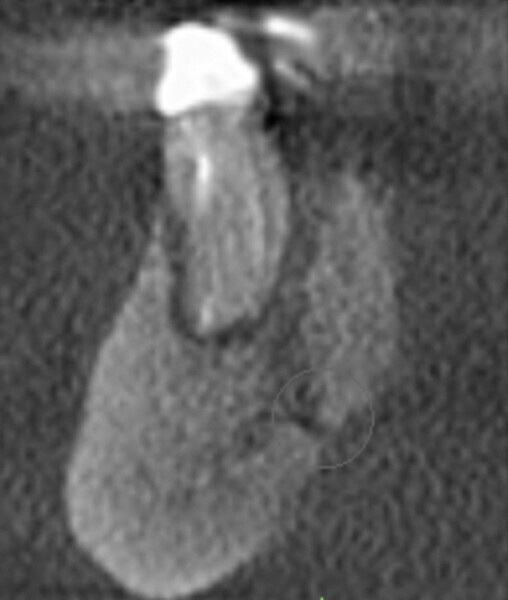

In this first case, the patient, who lived abroad and was unable to travel at the time, had swelling of her right mandible (Fig. 6), had had breast cancer and had been under bisphosphonate treatment for 18 months. She sent a panoramic radiograph (Fig. 7), and this showed a minor apical infection of the mandibular right first molar, which had undergone endodontic treatment. A CBCT scan was then taken, and from examining her scan, we could clearly see an area of bone densification (Fig. 8). This should be a red flag because this indicates the start of bone necrosis.

Fig. 8: Axial view of the CBCT scan showing a small apical infection of the mandibular right first molar, surrounded by an area of dense ossification extending over a large part of her mandible.